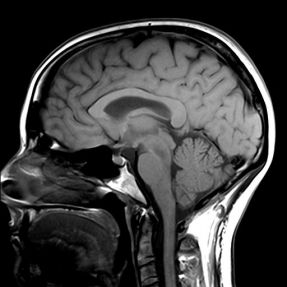

MRI of the Brain